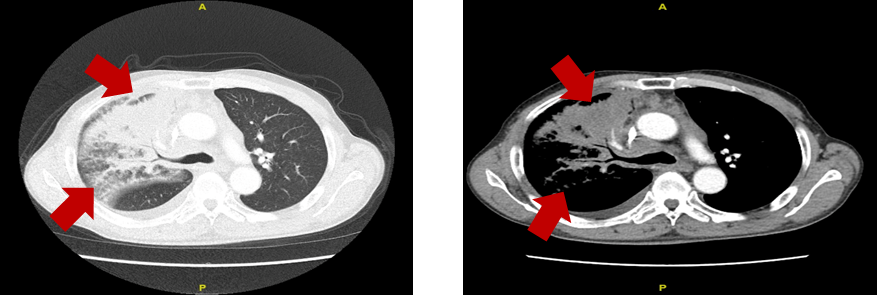

胸部增强CT:右肺中叶、肺门周围见大片软组织密度,强化不均匀,右肺支气管壁明显不规则增厚,管腔部分变窄、闭塞,纵隔内见多发肿大融合淋巴结,右侧

胸部增强CT:右肺上叶、中叶及肺门周围软组织密度影范围增大,纵隔内见多发肿大融合淋巴结,心包积液,右侧胸腔大量积液。